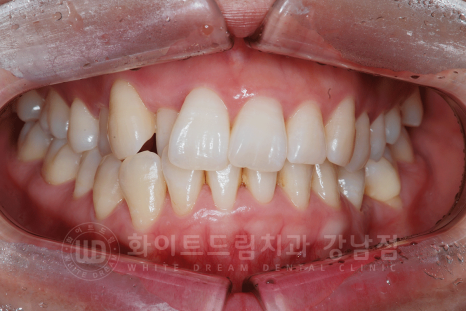

덧니(crowding)이 심하신 상태 + 35번 치아가 상실된 상태로 본원을 찾아주신 환자분의 케이스 리뷰입니다.

덧니가 심해서 입이 항상 부자연스러워요.

입을 다물 때 항상 턱에 주름이 지고, 덧니 때문에 입이 콤플렉스예요.

라는 주소로 내원을 해주셨는데요.

가만히 입을 다물고 있는데도, 덧니로 인해 입에 항상 힘이 들어가고 비대칭적인 안모 형태를 가지신 분이었습니다.

교정 후에는 입매 라인에 힘이 빠지면서 자연스럽게 입이 다물에 지는 것이 확인되실 겁니다.

환자분의 초진 구내 사진입니다.

치아의 틀어짐과 덧니가 심한 상태였고, 몇몇 치아는 교합이 반대로 물리는 치열이었고 상/하악 치아의 교합은 좋은 상태였습니다.

교정 후 입매 라인 변화입니다.

동일 인물이며 동일 환경에서 촬영되었습니다.

콤플렉스였던 사나워 보이는 치열과 부자연스럽던 입매 라인도 모두 개선되었고

무엇보다 임플란트 치료까지 동반했는데 치료가 빨리 끝나셔 환자분이 굉장히 좋아하셨답니다. ^^